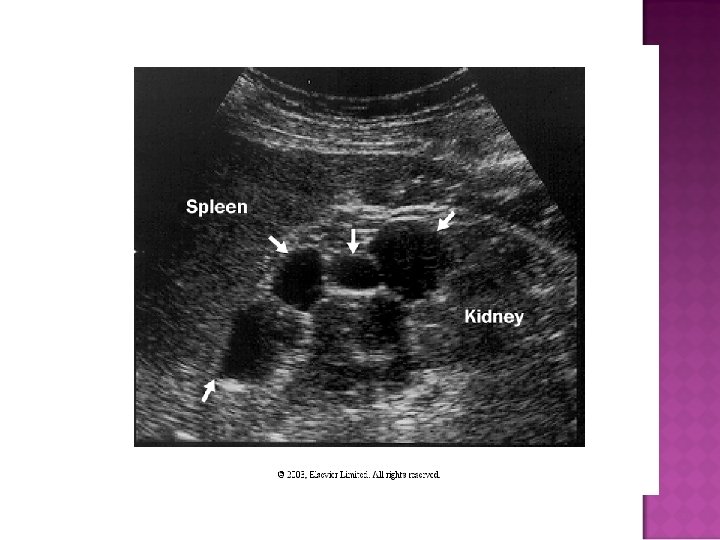

Easy diagnosis in overt disease: flank pain, positive family history, CRI, large kidneys with multiple bilateral cysts on CT or sonogram Cysts in liver, pancreas, and spleen What do you do with otherwise unexplained CRI, hematuria, with negative family history?